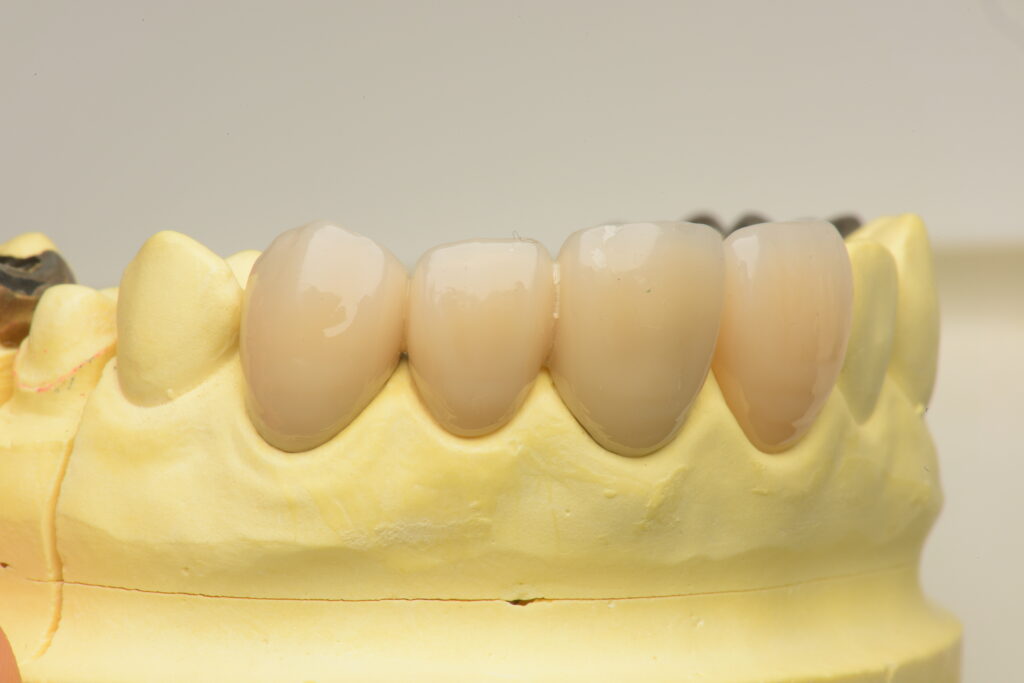

そこから、強度を少し落として透明感を出したジルコニアが出てきて、表面に色を塗って焼くだけでも綺麗な歯を作れるようになったので、セラミックを盛らなくても違和感の少ない被せ物ができるようになってきました🦷✨

自由診療での接着ブリッジ(当院での自例)

主にセラミックやジルコニアを使った治療が多く

外れる可能性、割れる可能制はありますが、金属を使わないので見た目がきれいになります。

実際の当院での事例ですが

この方も乳歯が残っていたのが抜けてしまい、当時県外で保険診療で接着ブリッジを入れたそうです。

上下の歯をやりかえていきましたが、上の歯は虫歯や奥の削られていた歯の形の問題で通常のブリッジをセラミックで修復、下の歯は接着ブリッジでやりかえました。